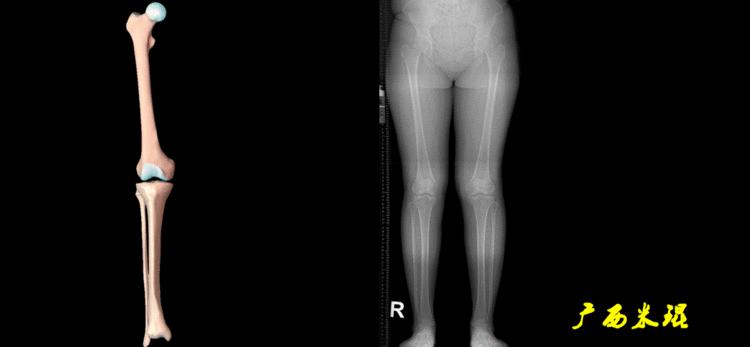

4、画出与机械轴相关的角度

股骨近端外侧角(LPFA):沿股骨头中心与大粗隆最高点划一直线,连接股骨头中心与膝关节中心划一直线(机械轴),两者之间形成的外侧夹角,正常为90°±5°。

股骨远端外侧角(mLDFA):股骨内外侧髁远端切线(关节线)与股骨头和膝关节中心的连线(机械轴)两者之间形成的外侧夹角,正常为87°±3°。

胫骨近端内侧角(mMPTA):胫骨内外侧平台切线(关节线)与股骨头和膝关节中心的连线(机械轴)两者之间形成的内侧夹角,正常为87°±3°。

胫骨远端外侧角(mLDTA):胫骨远端切线(关节线)与下肢力线(机械轴)两者之间的外侧夹角,正常为89°±3°。

5、画出与解剖轴相关的角度

解剖股胫角(aFTA):股骨干下段轴线(解剖轴)与胫骨上段轴线(解剖轴)在膝关节所形成的夹角,正常为174°±1°。膝关节OA的畸形常常由于一侧软组织及关节的过度磨损所致,临床多为内侧磨损过度,因此表现为轻度膝内翻畸形,X线表现为解剖股胫角小于174°,而胫骨角正常。

解剖股骨远端外侧角(aLDFA):股骨干下段轴线(解剖轴)与股骨内外侧髁远端切线(关节线)在膝关节外侧所形成的夹角,正常为81°±2°。大多数膝外翻患者的畸形发生于股骨下端,表现为股骨远端外侧角小于正常值。

解剖胫骨近端内侧角(aMPTA):胫骨内外侧平台切线(关节线)与胫骨解剖轴两者之间形成的内侧夹角,正常为87°±3°。由于胫骨解剖轴与机械轴几乎一致,所以一般解剖胫骨近端内侧角与机械胫骨近端内侧角一致。

解剖胫骨远端外侧角(aLDTA):胫骨远端切线(关节线)与胫骨解剖轴两者之间的外侧夹角,正常为89°±3°。由于胫骨解剖轴与机械轴几乎一致,所以一般解剖胫骨远端内侧角与机械胫骨远端内侧角一致。

解剖胫骨近端外侧角(也叫aMPTA):胫骨干上段轴线与胫骨平台切线(关节线)在膝关节外侧所形成的夹角,常称为胫骨角,正常为87°±3°。大多数膝内翻患者的畸形发生于胫骨上端,表现为胫骨角大于90°。严重的膝内翻畸形发生在整个下肢,股骨干及胫骨干都有可能形成向内弯曲的弧形。